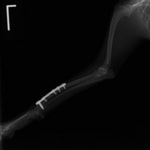

トイプードル 右遠位橈尺骨短斜骨折のALPSによる内固定

Locking Compression Plate

LCPは、スクリュー(ネジ)とプレート(金属の板)をロックする特殊な構造により骨折部位を固定する新しい世代のプレートシステムです。ひとつのホールでロッキングスクリューとスタンダードスクリューの使用を選択できるユニークな構造をしているため、骨折断端間の圧迫を目的とした従来型プレート固定法に加え、高い角度安定性を有するロッキングスクリューを用いた固定法の選択が可能です。従来のプレートシステムでは困難だった部分の骨折や癒合不全の症例に高い治療効果をもたらします。

Advanced Locking plate system と Locking compression plate system

当院ではAdvanced Locking plate system(ALPS)と、Locking compression plate system(LCPS)という骨接合法で骨折症例の治療を行っています。

Advanced Locking Plate System

従来型のプレートのように広い面積で骨と接するプレートを用いて固定を行った場合、プレート下の骨はプレートとの接触面において血行が絶たれ壊死し、それがリモデリングされると骨密度が低下する。この骨密度の低下防ぐために、骨折部局所への血行を温存することの重要性が近年改めて認識されるようになってきている。Advaed Locking Plate System (ALPS)は従来型のプレートシステムの欠点を改良し、より使いやすく、より骨への血行を阻害しないようにというコンセプトで作られた。